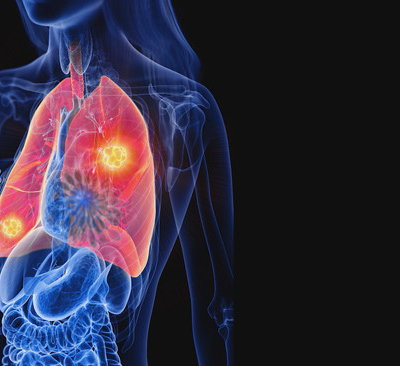

오늘은 우리 몸의 호흡을 책임지는 폐에 대해 이야기하려 합니다. 특히, 폐에 발생하는 악성 종양인 폐암의 초기 증상에 대해 자세히 알아보려 합니다.

폐암 초기증상 폐암은 초기 증상이 감기나 다른 호흡기 질환과 비슷해 간과하기 쉽습니다. 하지만 조기 발견이 치료에 매우 중요하기 때문에, 미묘한 변화라도 놓치지 않는 것이 중요합니다. 지금부터 폐암의 주요 초기 증상들을 꼼꼼히 살펴보고, 건강을 지키는 첫걸음을 함께 시작해 볼까요?

폐암 초기에는 특별한 증상이 없는 경우가 많지만, 암이 진행되면서 다양한 신호를 보낼 수 있습니다. 다음은 폐암 환자들이 흔히 경험하는 10가지 주요 초기 증상입니다.